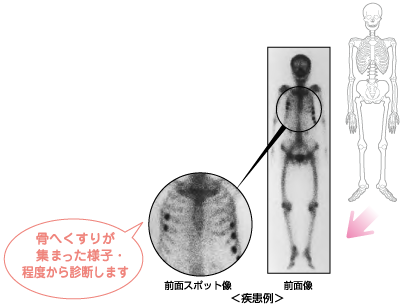

全身骨シンチグラフィ 乳癌 肺癌 前立腺癌等の骨転移病巣の検出

主な核医学検査 骨 骨シンチグラフィ 核医学検査のご案内 医療関係者

骨シンチグラフィーとは 佐賀大学病院放射線科アンオフィシャル

全身骨シンチグラフィ 乳癌 肺癌 前立腺癌等の骨転移病巣の検出

骨シンチグラフィによる骨転移の診断 Bone Scan Ct Mri画像診断